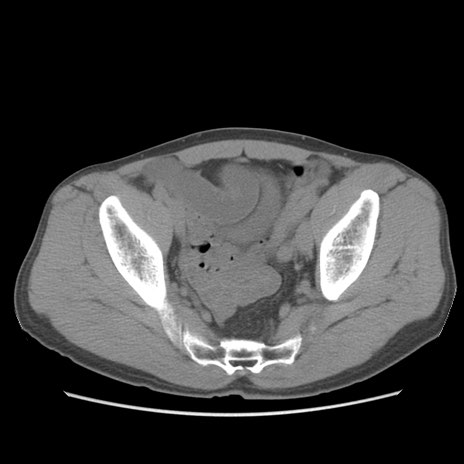

症例56 CT(横断像)

脂肪ウインドウ